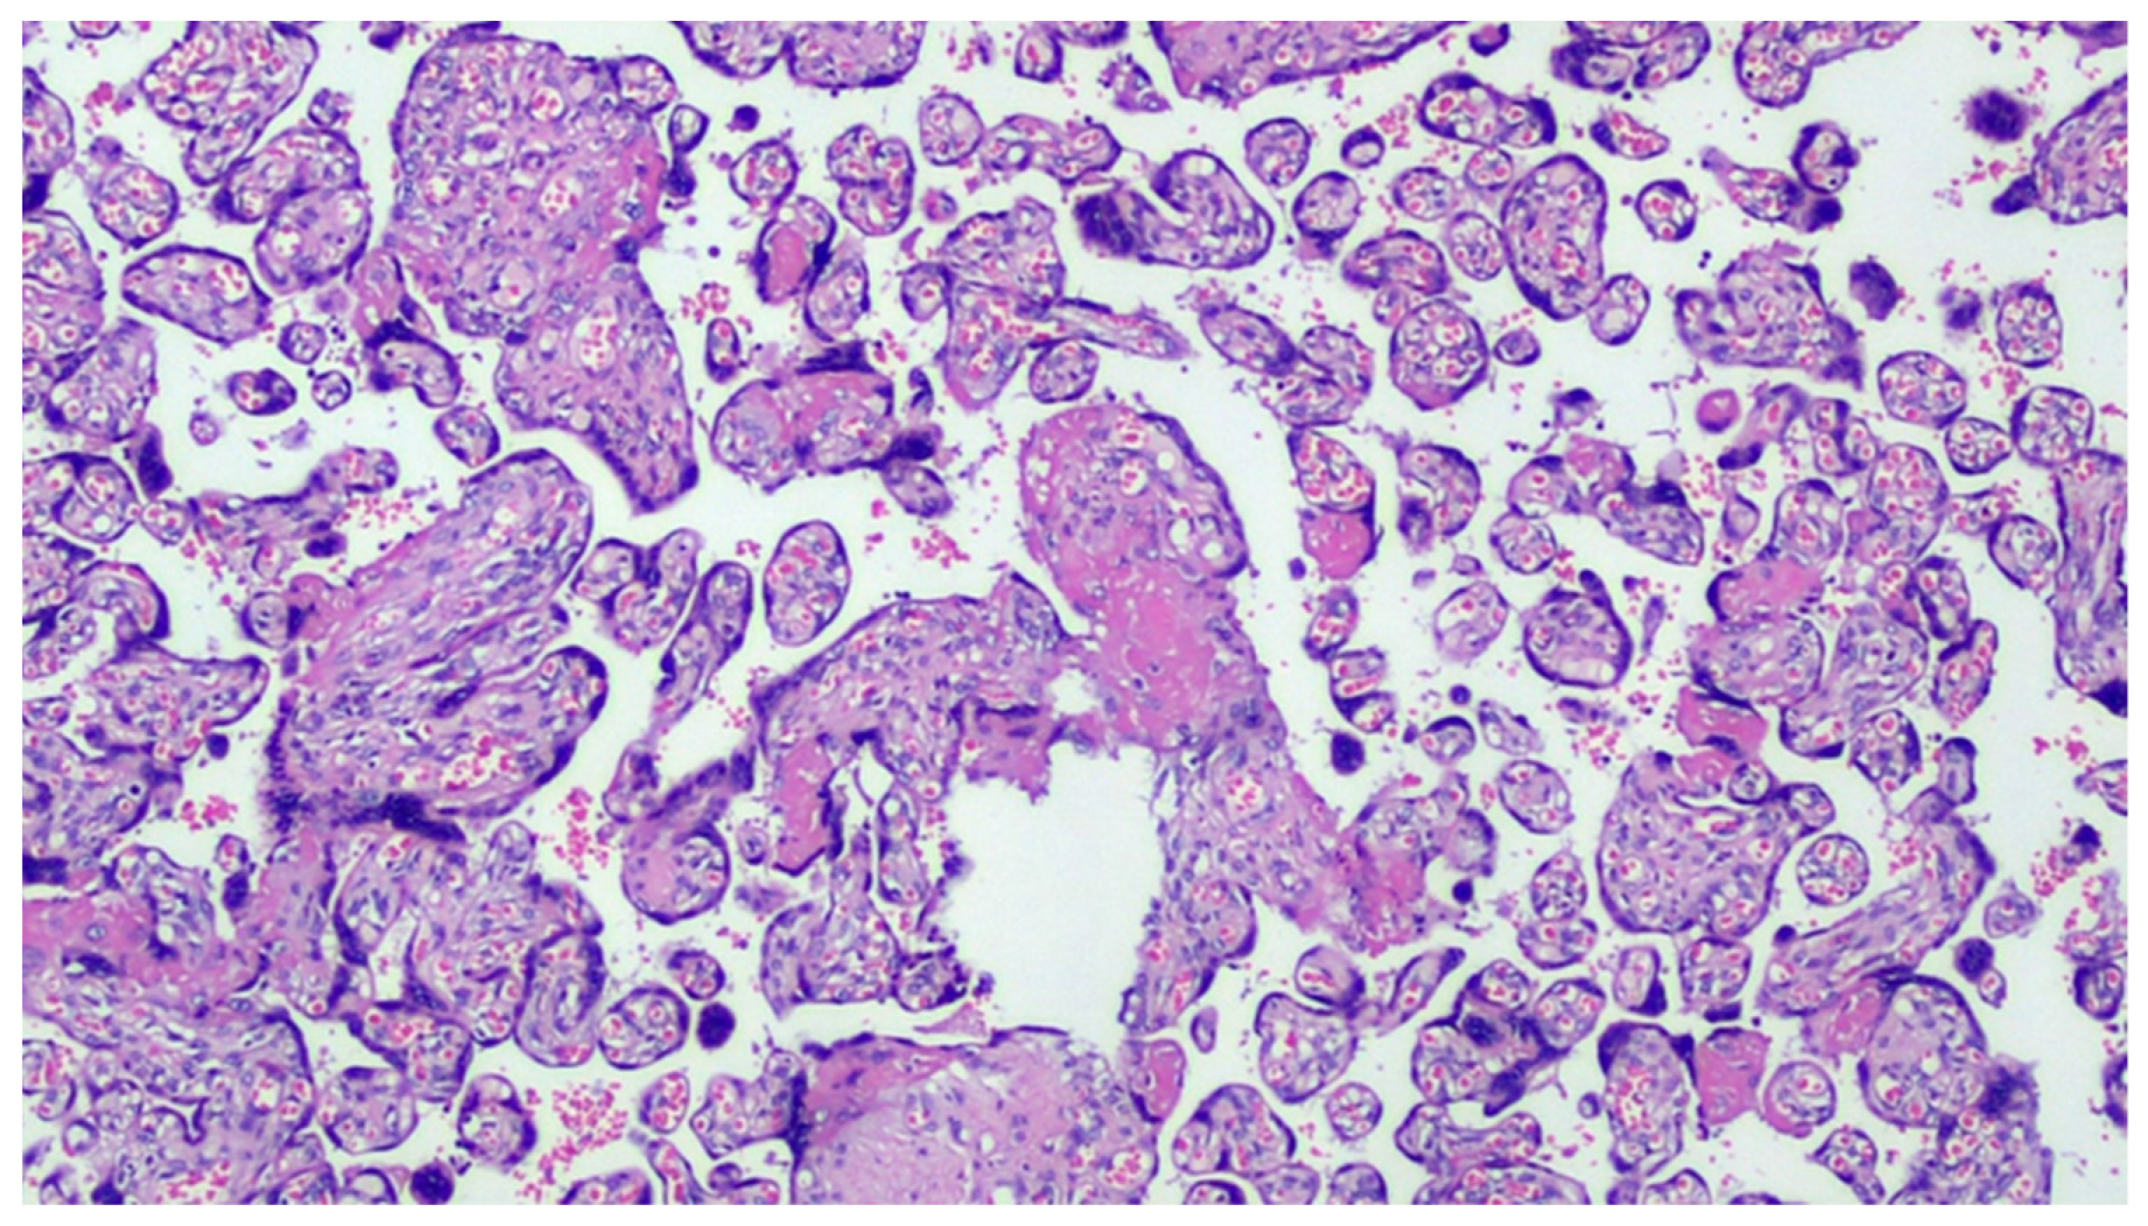

Figure 1.

COVID-19-positive mother placenta. Terminal chorionic villi with poor vascular component (distal hypoplasia of the villi due to early maternal malperfusion) with increased syncytial nodes. Some villi show a deposition of fibrin in the intervillar space with progressive reduction of the villi (H&E, Hematoxylin and Eosin, 100×).